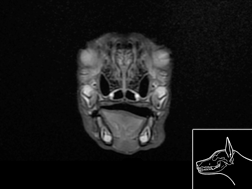

Atlas cérébral du chien IRMT2

IRM T2

>> 17 coupes